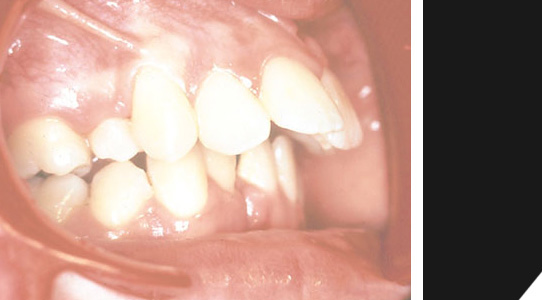

Schneidezähne oben stehen zu eng, untere Front besteht nur aus drei Zähnen.

Eine deutliche Fehlstellung des Frontbereichs...

Im unteren Bereich sind nur drei Frontzähne vorhanden...

Zudem kommt noch ein starker Überbiss...